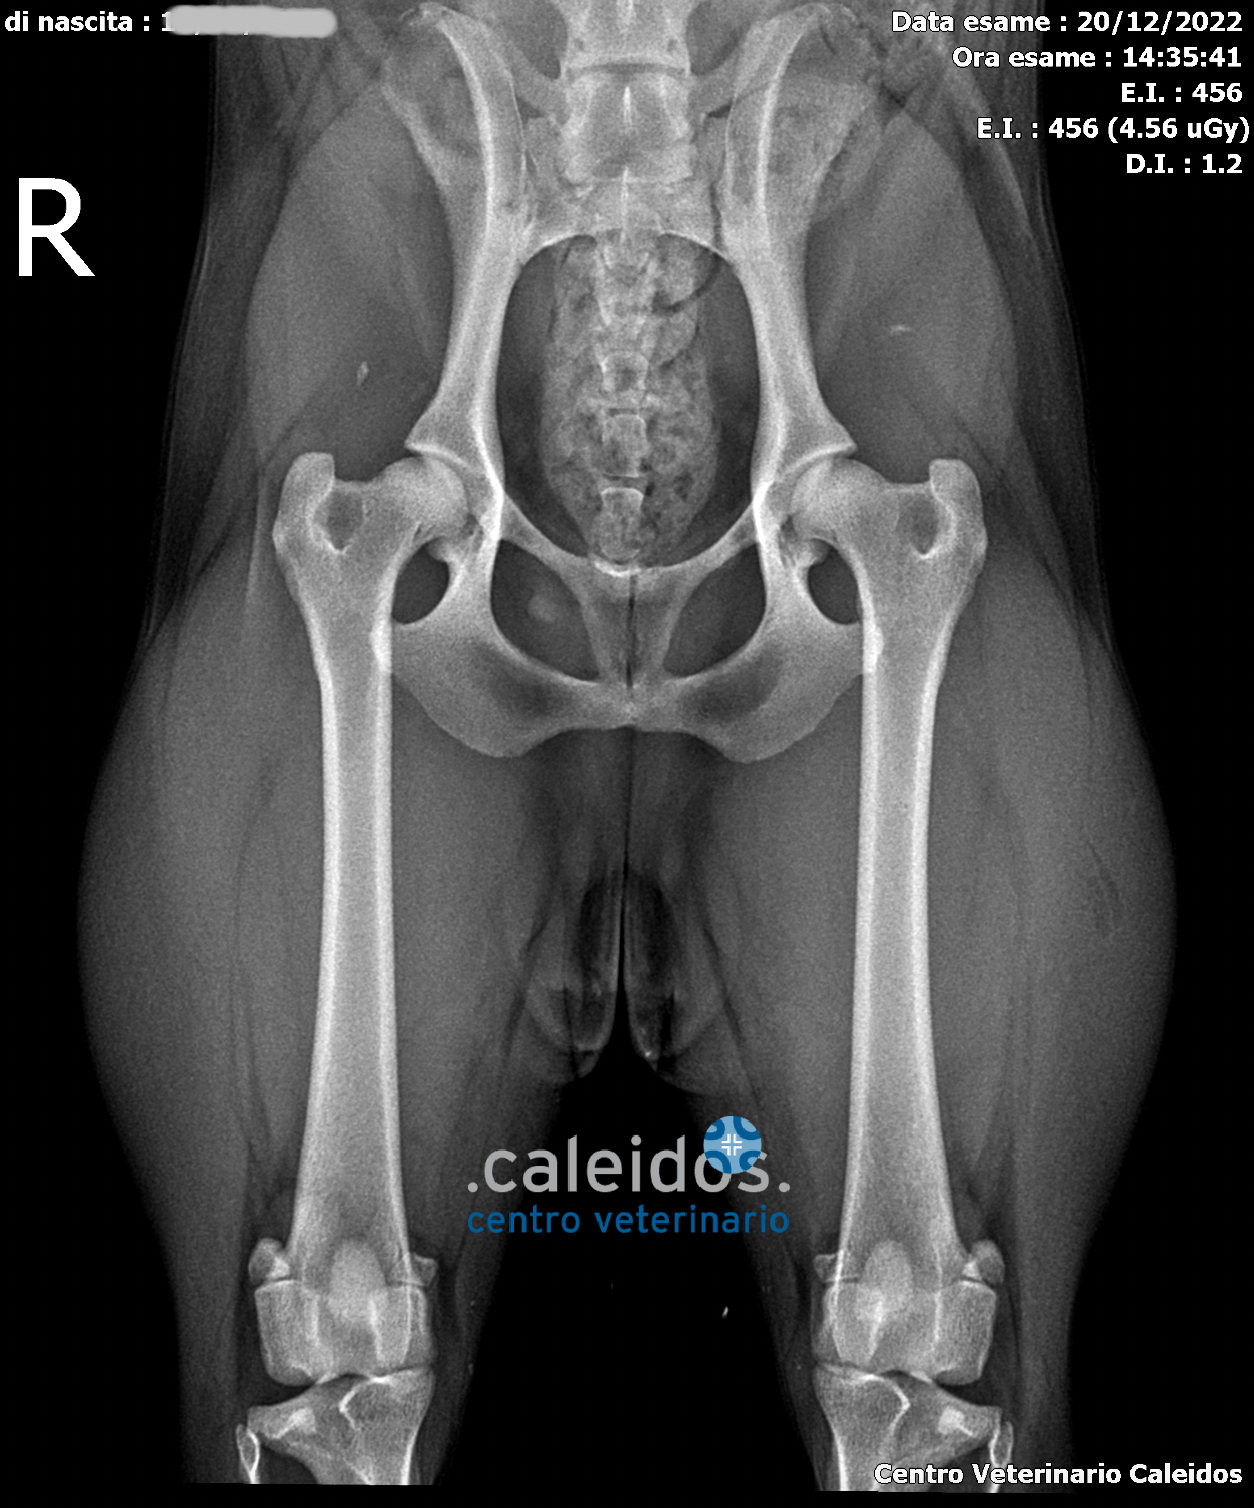

At Caleidos clinic we can perform radiographic studies for dysplasia of the hips, elbows, patellar luxation and many other hereditary skeletal pathologies, thanks also to authorisation for the official reading of this type of pathology obtained for both Ce. Le.Ma.Sche and FSA.